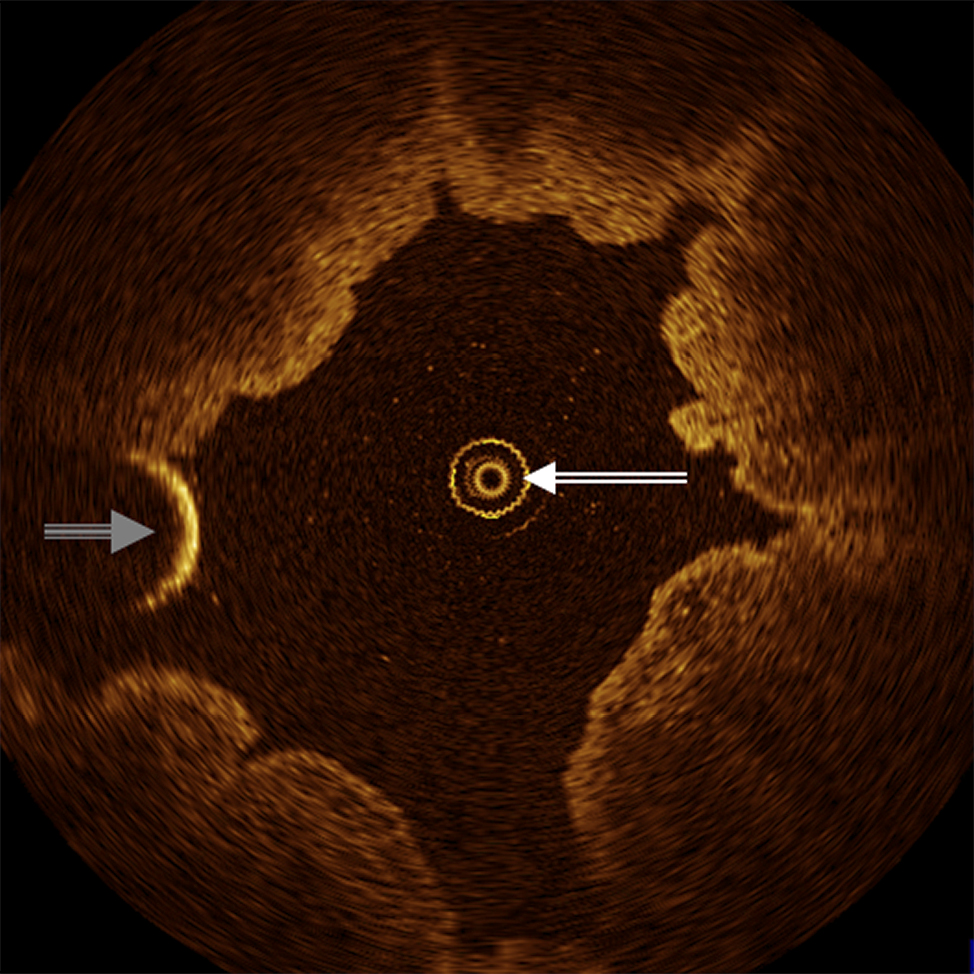

Figure 1. Axial, cross-sectional OCT image of human upper ureter in vivo demonstrates OCT probe (double-lined white arrow) in the center and wire guide of ureterorenoscope (triple-lined grey arrow) on the side of the ureter lumen.

OCT was technically successful and acquired images in all human UUTs examined in vivo (Fig. 1). Respective OCT probe positions within the ureter immediately visualized through the rigid ureteroscope, such that ureteroscopy could guide OCT image sampling. However, neither the tip of the OCT probe nor the pilot light was visible to the endoscopist when applying the UK.